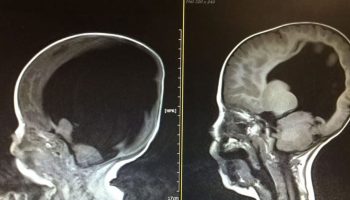

Ребенок родился «без мозга». Спустя три года, врачи в недоумении, после просмотра снимка головы малыша

2.8к.